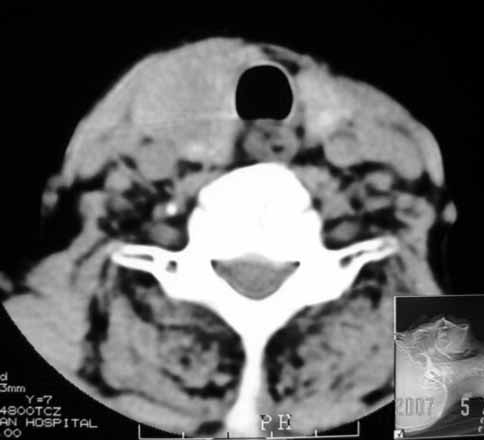

以下是引用jw-830在2007-5-24 15:33:00的发言:[br]右侧甲状腺增大,内可见低密度,病灶与周围软组织界线欠清晰,建议增强扫描除外甲状腺癌

以下是引用adams在2007-5-24 17:15:00的发言:[br]支持“ 右侧甲状腺增大,内可见低密度,病灶与周围软组织界线欠清晰,建议增强扫描除外甲状腺癌”。 [br] [br] [br][br] [br] [br]

以下是引用苯小孩在2007-5-24 15:26:00的发言:[br]左侧甲状腺腺癌或瘤,建议穿刺或核素进一步检查.